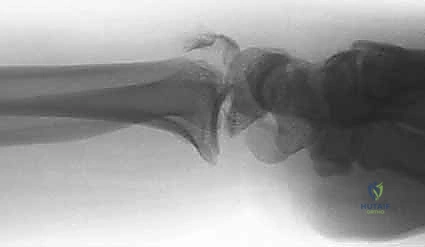

- الأشعة السينية (X-rays):

هي الخطوة الأولى لتقييم الكسر. يتم أخذ صور من زوايا متعددة (أمامية خلفية، جانبية، ومائلة) لتحديد موقع الكسر الأساسي ودرجة الانزياح والتقصير في عظم الكعبرة.